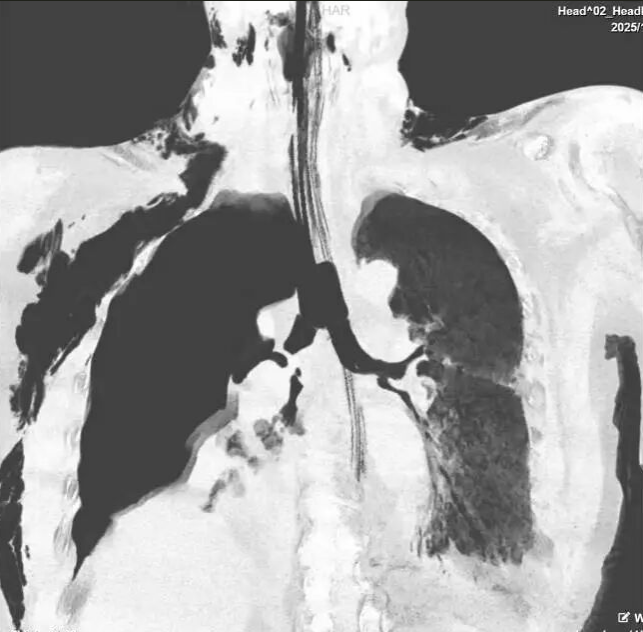

患者为中老年男性,因车祸引发严重胸部外伤,受伤后迅速出现呼吸困难。外院急诊胸部 CT 检查提示,患者疑似支气管断裂、双侧多发肋骨骨折及肩胛骨骨折,病情危急。经我院胸外一科丁翔副主任会诊评估后,患者在气管插管呼吸机辅助呼吸状态下,由 120 紧急转入我院重症医学科(RICU)接受进一步抢救。

入院后,RICU 余述凤主任立即组织团队为患者行床边气管镜检查,明确诊断为 “右主支气管完全断裂”。随后,医院医务科迅速牵头启动多学科(MDT)讨论,RICU、胸外科、生命支持中心、麻醉科、介入肺脏科 / 内镜中心、呼吸科、影像科、手术室等科室专家共同研判病情。

在 ECMO 持续辅助下,胸外一科丁翔副主任团队在王保明主任指导下开展胸腔探查,进一步证实 “右主支气管完全断裂、右上肺实变无功能”。历经 3 小时精细操作,手术团队成功为患者实施 “右肺上叶切除 + 右中间段支气管、右主支气管断端吻合术”。